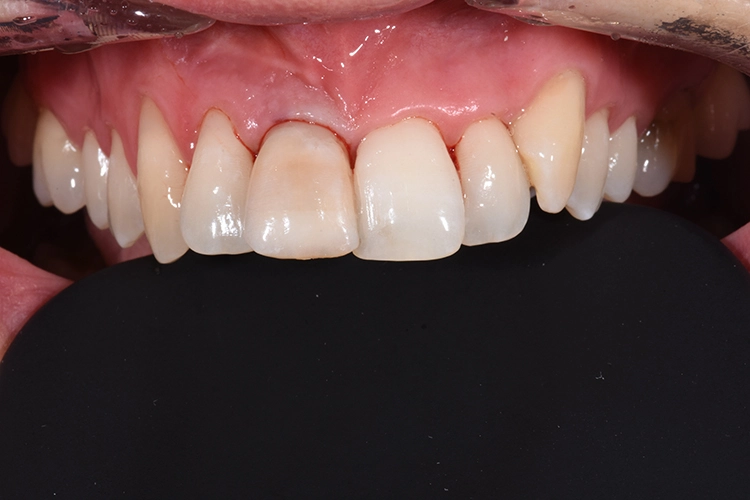

Deutlich auffallend und für die Patientin sehr wichtig war die anatomisch individuelle Zahnstellung des Zahnes 11. Um dem Wunsch der Patientin auf eine für ihr Umfeld unauffällige Behandlung gerecht zu werden, entschieden wir uns gemeinsam für eine Sofortimplantation mit einer provisorischen Sofortversorgung des Implantates. Kein Provisorium kommt der Natur so nah wie die Natur selbst und daher planten wir die Umarbeitung der Zahnkrone 11.

Nach der Lokalanästhesie wurde zunächst ein Kunststoff Jig hergestellt, der die Inzisalkante des Zahnes 11 mit denen der Nachbarzähne verbindet. Dieser dient zur späteren Positionierung der Zahnkrone, wenn diese zum Provisorium umgearbeitet wird und mit dem Implantat verbunden wird. Dieser Schritt ist besonders wichtig, da es für ein unauffälliges postoperatives Ergebnis auf die korrekte Positionierung des Zahnes ankommt und die Positionierungshelfer das Handling und den adhäsiven Verbund unglaublich vereinfacht (Abb. 20 und 21).